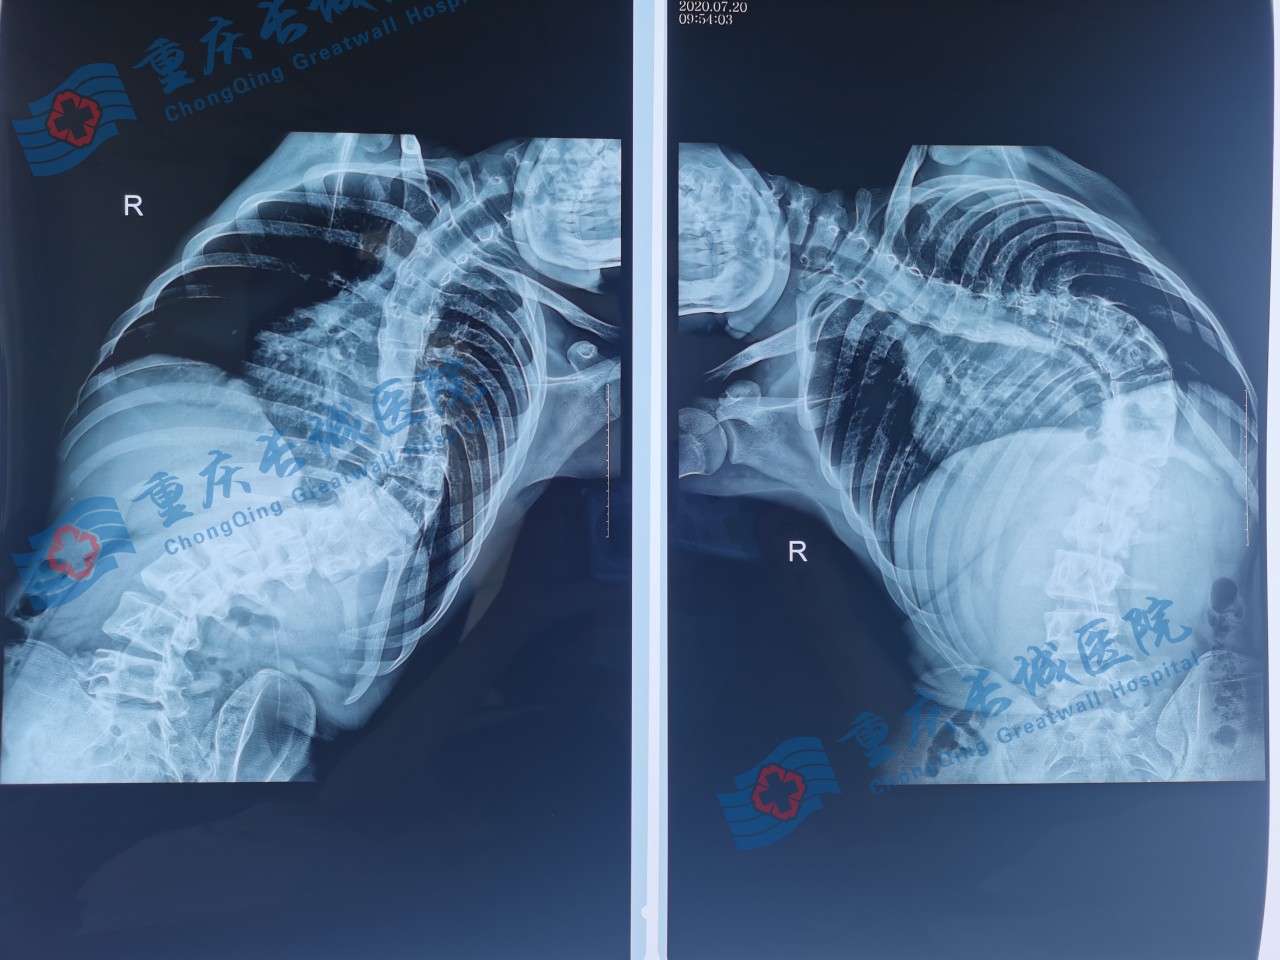

小圆术前

姓名:小圆 年龄:15岁 性别:男

入院诊断:特发性脊柱侧弯(青少年型)。

经过入院检查,骨科医生们为其制定了科学的手术方案:经后路切开脊柱矫形钉棒系统内固定术以及胸廓成形术。